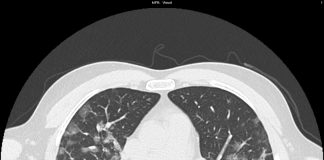

63-year-old male patient with no previous medical history. Exposure to Covid-19 patients. Fever, cough.

Respiratory failure (hypoxemia and hypocapnia). Leukocitosis. Nasal swab positive for SARS-CoV-2.

HRCT

Figura 1